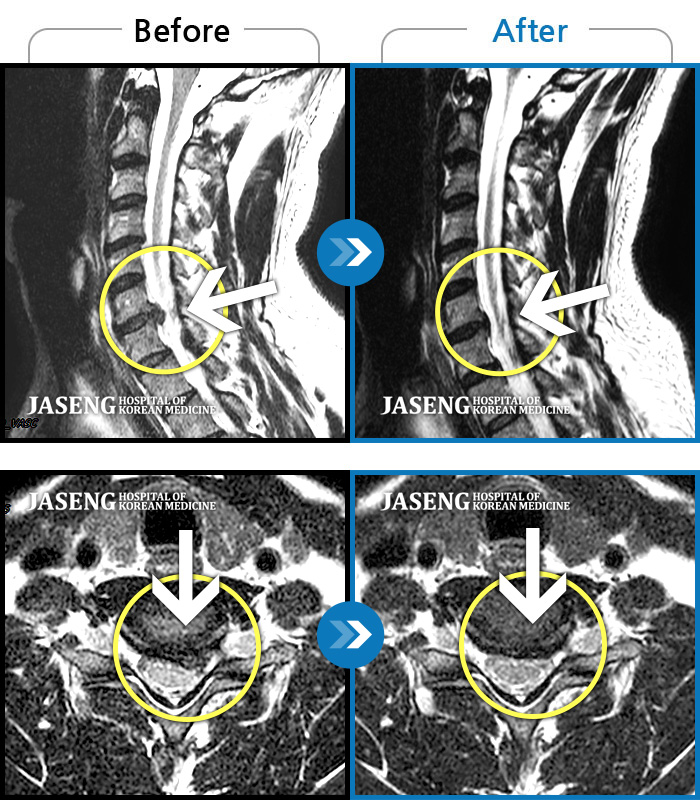

목디스크

강남 · 강만호 원장

양측 승모근 통증과 목 통증, 견갑골 통증으로 고개를 돌릴때 통증을 호소하는 환자였습니다.

촬영시기

2019.11.18 ~ 2024.07.30

2024.08.09